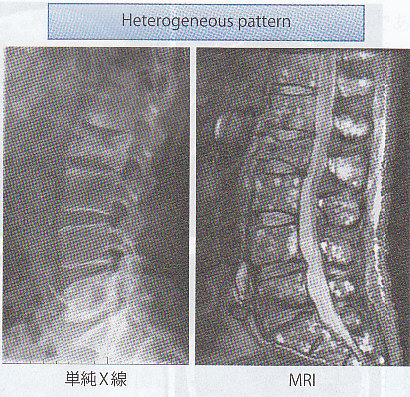

骨病変のスクリーニング検査としては、全身の単純X線検査を行い、溶骨性病変の有無を検討する。主に、頭蓋骨、肋骨、脊椎骨、骨盤、法腕骨、大腿骨の検査が行われる。多発性骨髄腫に特徴的な所見として頭蓋骨の打ち抜き像(punched-out lesion)が知られている。

MRIは骨の内部構造の描出に優れており、T1強調像低信号、T2強調像やSTIR像で高信号として見られる。